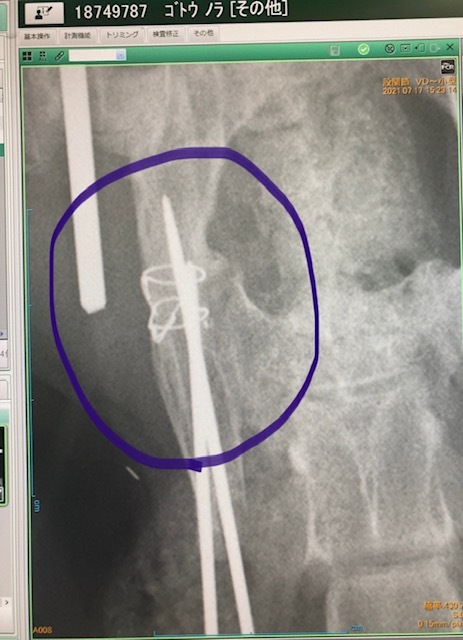

本日、レイちゃんのボルト摘出、避妊手術、血液検査等を行なってきました。先生曰く、問題なく骨が接合しており無事にボルト摘出を行えました。去勢手術も同時に行って頂きました(レイちゃんの負担になるかとも懸念しましたが麻酔が効いている間に一緒に行う事がベストと判断)。血液検査も行い、心配していた猫エイズに関しても陰性でした。2週間後に抜糸のみありますがこれでひとまずは無事に骨折治療を終える事が出来ました。皆様の篤いご支援に支えられた事に対し改めて深い感謝の意を申し上げます。有難うございました。明日以降順次ご支援頂きました皆様へリターン報告に入らせて頂きます。お待たせして申し訳ございませんがどうぞ宜しくお願い致します。

骨盤部分もしっかり接合(左)、左大腿骨も接合(右:太くなってます)していました。